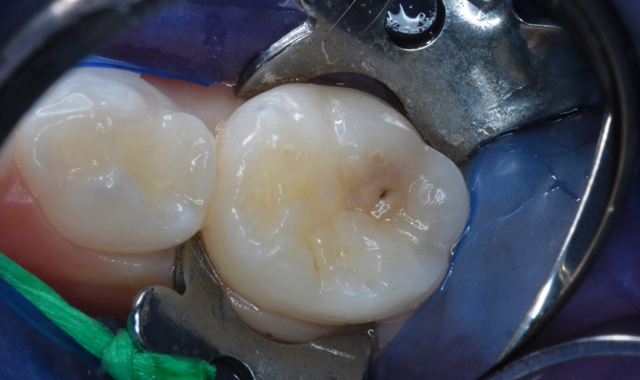

Fig. 3 Fig. 4

After appropriate local anesthesia, the tooth was isolated with a rubber dam, using the “slit dam” method (Fig. 2). Outline form was prepared using a high-speed diamond bur, exposing the extent of the caries lesion (Fig. 3). Carious dentin was debrided with slow-speed round burs and the cavity preparation was completed (Figs. 4 and 5).